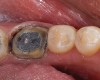

2. Flexure Risk Assessment

Next is the flexure risk assessment. Each tooth and existing restoration is evaluated for signs of past overt tooth flexure. Signs of excessive tooth flexure can be excessive enamel crazing (Figure 2), tooth and restoration wear, tooth and restoration fracture, microleakage at restoration margins, recession, and abfraction lesions. Often, the etiology is multifactorial and controversial. However, if several of these conditions exist, there is an increased risk of flexure on the restorations that are placed, which may overload weaker materials. Evaluation of this possibility is also based on the amount of remaining tooth structure. The more intact the enamel is, the less potential for flexure. The amount of tooth preparation can directly affect tooth flexure and stress concentration. There is much potential subjectivity in any observational assessment of clinical conditions; however, an assessment of flexure potential for each tooth to be restored is needed. A subjective assignment of Low, Medium, or High Risk for flexure is based on the evaluated parameters, as outlined below.

Figure 2  Image demonstrating excessive enamel crazing, leakage, and staining. Flexure, tensile, and shear risks would be medium to high. The substrate would depend   on preparation.

Figure 2